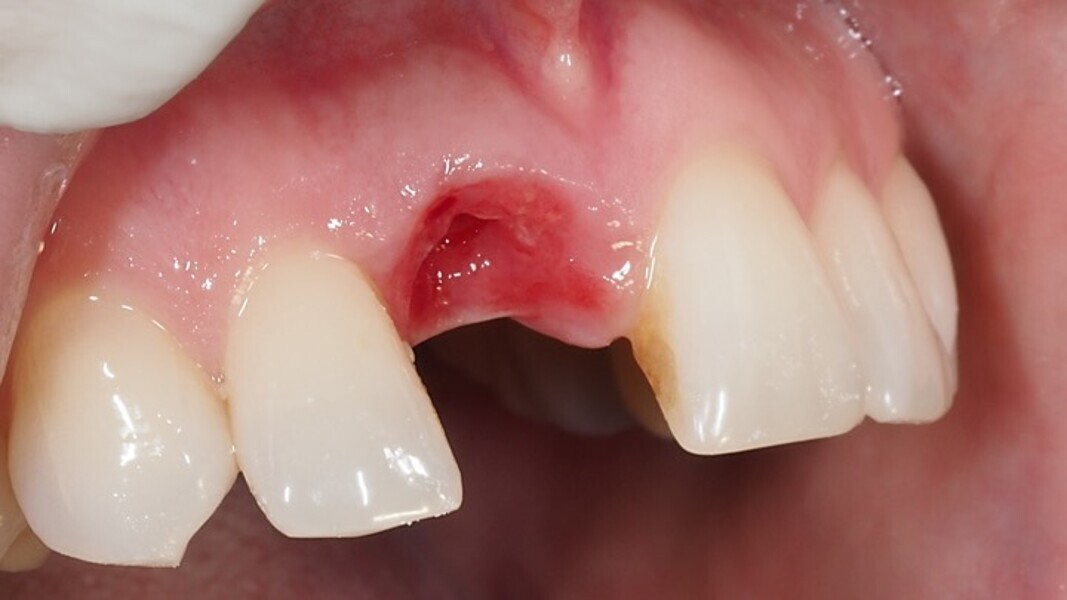

Figura 1. Atrofia de más del 50% de la pared vestibular en el diente 11 con infecciones de repetición de varios años de evolución.